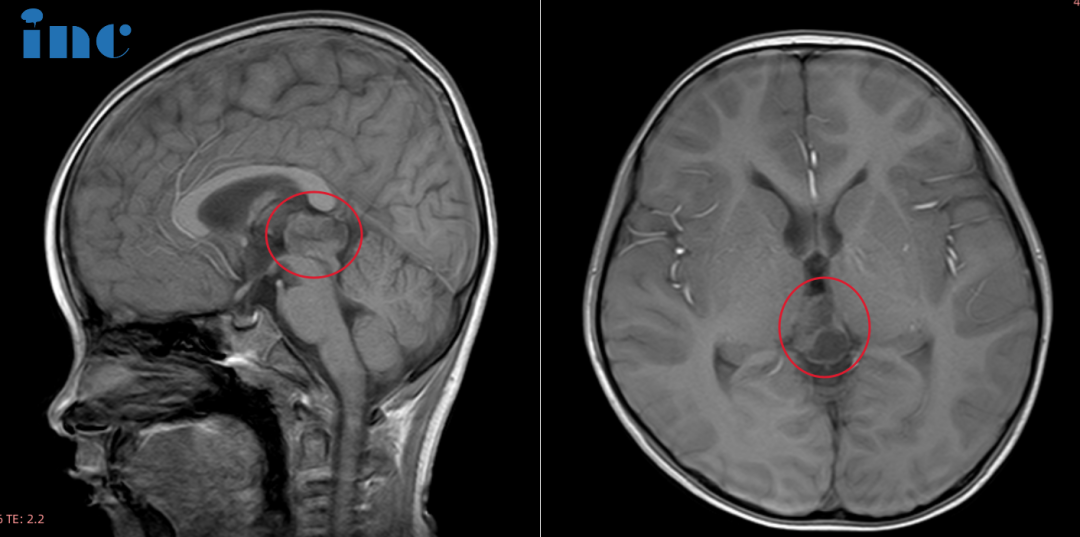

6岁的鑫鑫,在幼儿园意外摔破头皮就诊,CT检查后居然发现松果体区阴影和部分钙化灶,进一步进行MRI见检查后,发现22*14*17mm病灶。

在患者术前神经影像中提取相关信息是松果体区域成功手术的几个关键因素之一。常规MR图像可提供肿瘤的大小、程度和血管形成的信息,重要的还包括有关中脑、丘脑和小脑受压程度的有用信息。